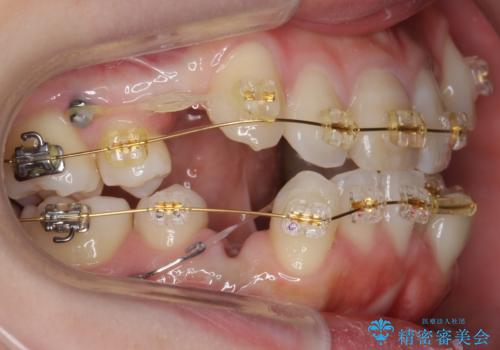

上下左右の小臼歯を抜歯し、ワイヤー矯正を行いました。

犬歯のコントロールが難しく、矯正用ミニスクリューを併用しました。

奥歯の歯の間が狭く、ミニスクリューを入れるのも難しい症例でした。

右上の前歯は変色もあり、神経の治療後にセラミックを被せる予定です。